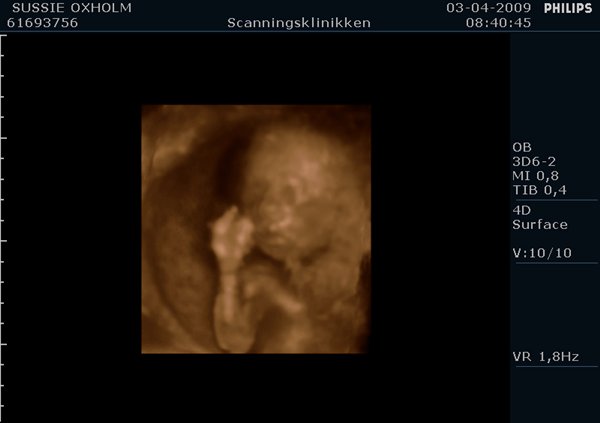

Her er Stellas nye Lillebror 27+3:

Til venstre ses lillesøster (Celina) i uge 27+3

Til højre på billederne er det storesøster (Bianca) i uge 29+3